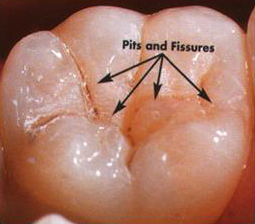

Fissure Sealants

These are special plastic protective coatings which are applied on the chewing surfaces of teeth with deep fissures. This forms a hard shield that keeps food and bacteria away and thus reducing the risk of developing decay.